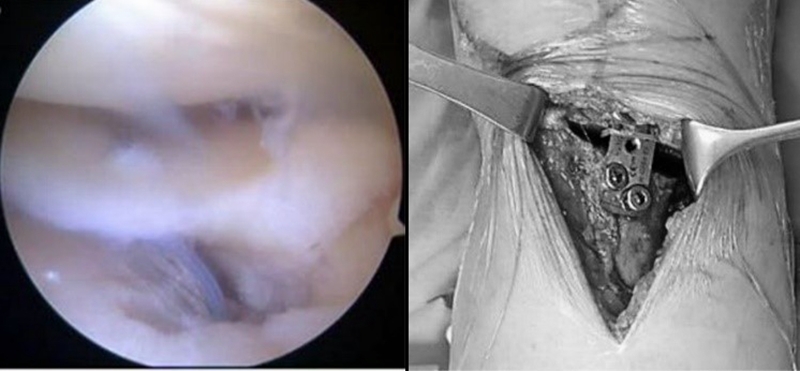

José等人采用内侧半月板后根修复联合OWHTO治疗内侧半月板后根部撕裂。他们认为在截骨术中松解内侧副韧带有利于内侧关节间隙的打开和修复半月板根部的操作,同时内侧间室减压有利于根部愈合,保证术后更快的恢复[2]

图2

Young等人采用改良Mason-Allen缝合技术联合OWHTO治疗内侧半月板后根撕裂。二次关节镜检查显示根部完全愈合率为64.7%,部分愈合率为29.4%,失败率为5.9%,联合手术抑制了骨关节炎的进展[3]

图3